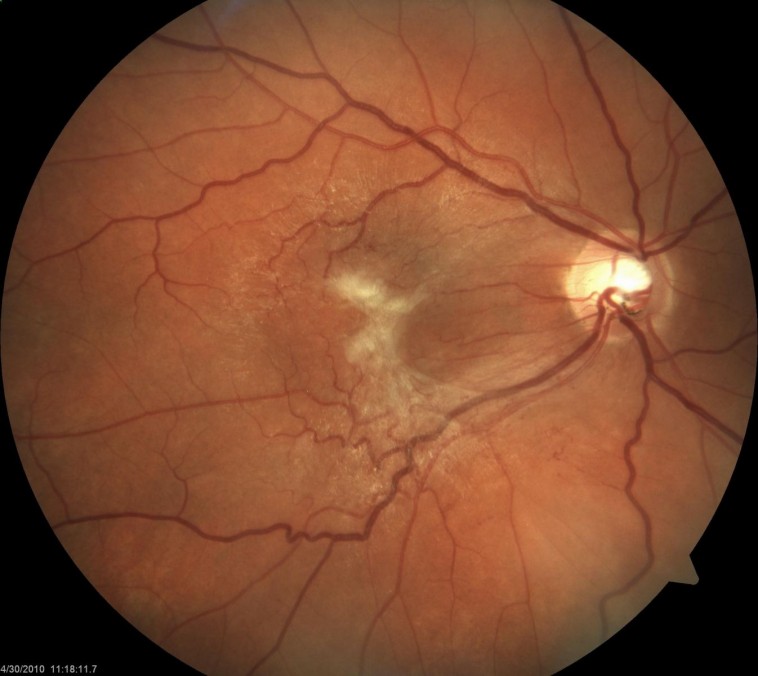

Görme merkezi önünde zar oluşumu:

(Makula zarı, Maküler Epiretinal Membran, Macular pucker)

Makula önü zarı, detay görmeyi sağlayan, görme merkezi (makula) önünde ince bir zar tabakasının oluşmasıdır.

Çoğu zaman makuladaki retina önündeki zarlar çok ince olduğundan hiçbir belirti vermeden yıllarca sessiz kalabilirler. Zamanla zarda gelişen kalınlaşma görme merkezinde çekintiye yol açarak görmede bulanıklaşmaya, cisimlerin eğri görülmesine neden olurlar.

Retina anjiyografisi ve OCT (Optik koherenz tomografi) tetkiki ile Makula önü zar teşhisi konulur.

Bazen makula önü zarı zamanla kalınlaşır, retinaya çekinti uygular ve görme kalitesini bozar, bulanık ve eğri görme gibi şikayetlere neden olur. Makula önü zarı tedavisinde amaç bu zarı olduğu yerden kaldırmakır. Makula önü zarı tedavisinde kullandığımız vitrektomi cihazlarındaki gelişmeler uyguladığımız teknikde devrim sayılabilecek değişikliklere imkan yartamıştır. Kullandığımız enstrumanlar o kadar incelmiştir ki ameliyat bitimde dikiş kullanma ihtiyacı önemli ölçüde ortadan kalkmıştır. Bu durum ameliyat süresinin kısalmasına, yara iyleşmesinin hızlanmasına imkan yaratmaktadır.